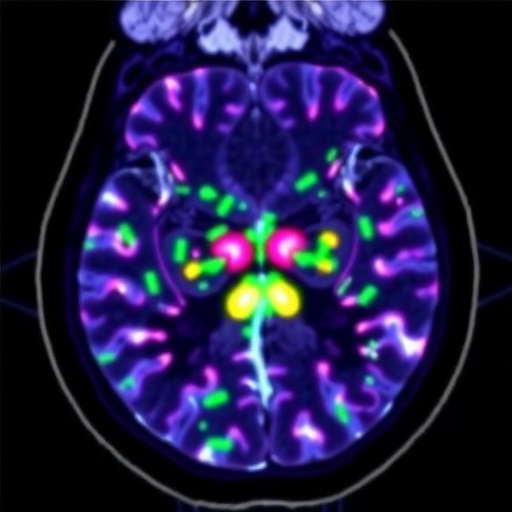

The research team, helmed by Professor Tim Witney from the School of Biomedical Engineering & Imaging Sciences, engineered a tracer based on carnitine, a pivotal molecule in fatty acid metabolism. Carnitine facilitates the shuttling of long-chain fatty acids across the mitochondrial membrane, a critical step for β-oxidation and subsequent ATP production within the cell. By tagging carnitine with a radioactive isotope, the team created a unique PET imaging agent capable of revealing real-time fatty acid utilization in living organisms, thereby providing an unprecedented window into metabolic fluxes associated with health and disease.

This advancement was rigorously demonstrated through preclinical models that showcased differential uptake of the carnitine-based tracer in various tissues, confirming its capacity to map lipid metabolism in physiological and pathological contexts. In particular, the tracer’s uptake was markedly elevated in certain aggressive tumor subtypes, emphasizing these cancers’ ability to harness fatty acids for energy production alongside glucose. Such findings challenge the entrenched view that cancer cells predominantly rely on glycolysis, opening new perspectives on tumor biology and metabolic heterogeneity.